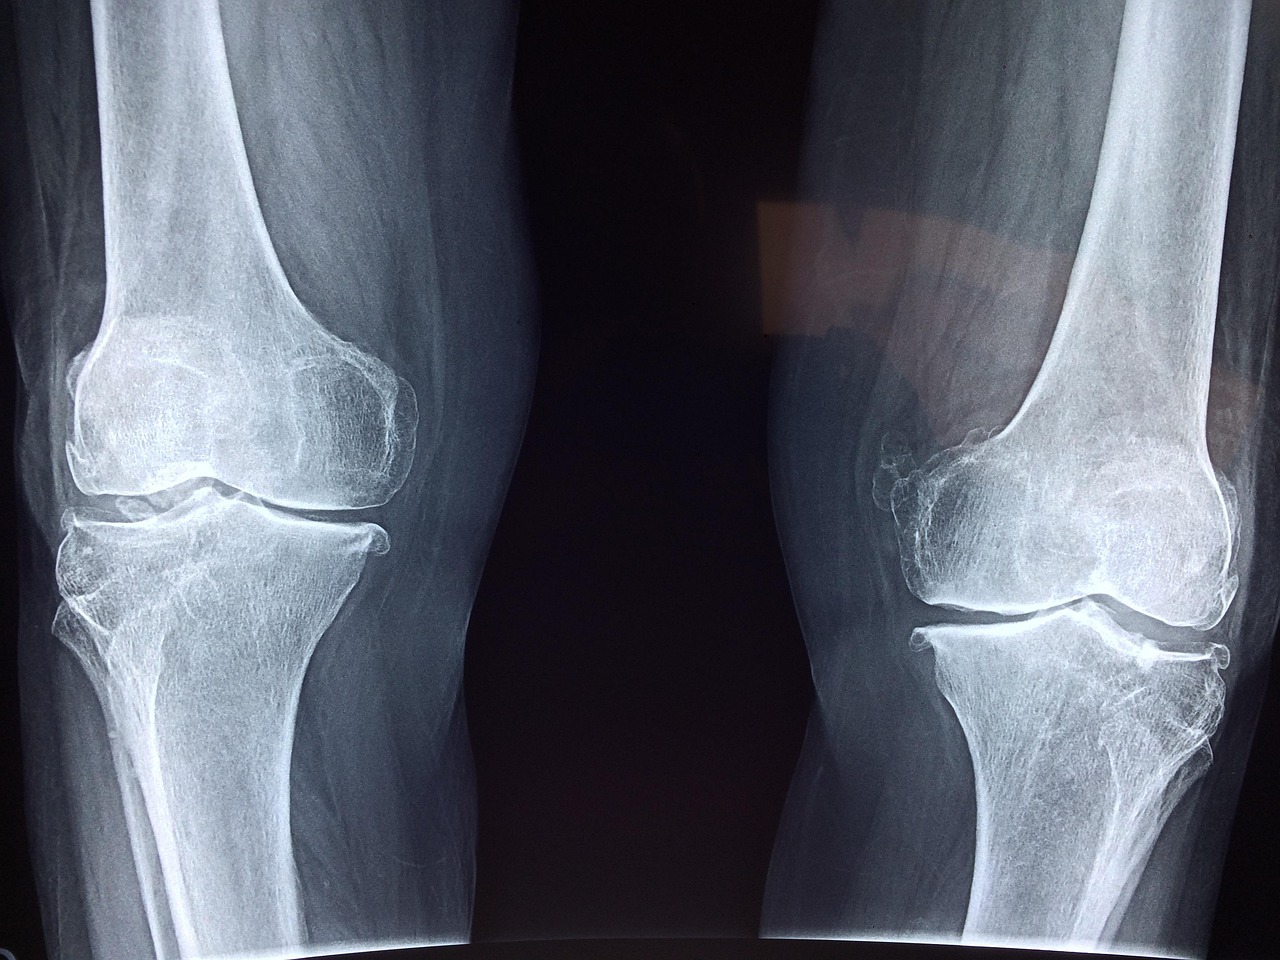

무릎 인공관절 수술, 준비가 회복을 좌우합니다

무릎 관절 통증이 심해 일상생활에 지장이 생길 정도라면 인공관절 수술을 고려하게 됩니다. 하지만 수술 전 알아두면 좋은 정보와 준비 사항들이 있습니다.

- 무릎 관절 연골이 거의 닳아 뼈끼리 마찰이 생기는 경우